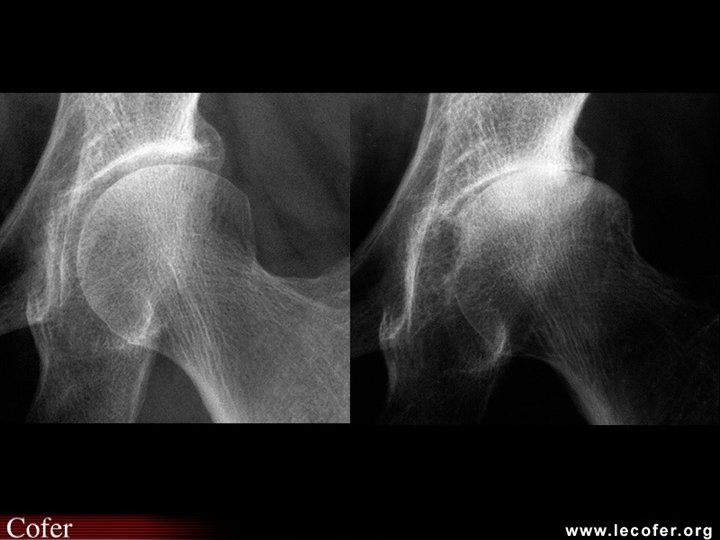

Coxarthrose Clinique • Debout – Recherche boiterie, – Attitude vicieuse, en flexum ou en rotation externe • Couché – douleur et/ou limitation douloureuse lors mobilisation (flexion / RI / RE) • La radiographie – Cliché bassin debout de face – Profil